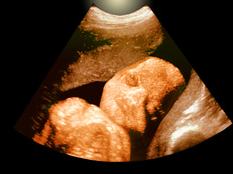

A legnagyobb veszélyben persze a kéthónaposnál fiatalabb babák vannak, akik még semmilyen oltást nem kaptak. Az ő védelmük céljából vetődött fel a terhes nők beoltása a harmadik trimeszterben. A terhesség ezen szakaszában ugyanis az anyai antitestek átjutnak a méhlepényen, és ezáltal védelmet jelentenek a magzatnak is. Az amerikai hatóságok a tetanusz, diftéria (torokgyík) és acelluláris pertussis (szamárköhögés)-oltást javasolják erre a célra.

A kutatások szerint a terhesség harmadik harmadában adott szamárköhögés elleni oltás nem jár gyakoribb születési komplikációkkal. Az oltást először a 2010-es járvány után kezdték javasolni a terhes nőknek – ebben az évben ugyanis tíz oltatlan csecsemő meg is halt a betegségben. 2012-ben a kaliforniai terhes nők mindegyikének javasolták az oltást, akkor is, ha ők eredetileg be voltak oltva a betegség ellen, hiszen itt a cél nem az anya, hanem az anya immunrendszere lévén a születendő baba immunizálása.